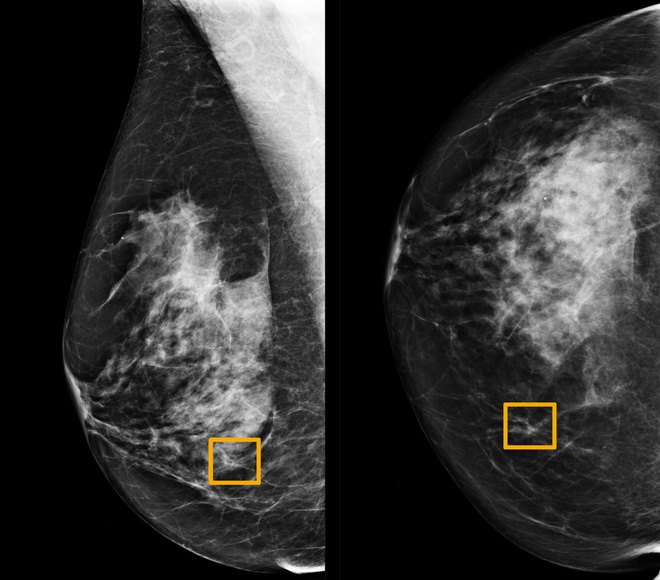

Ô vàng là nơi mà hệ thống trí tuệ nhân tạo cho rằng có ung thư vú. Ảnh: Đại học Northwestern. |

Kết quả nghiên cứu cho thấy tỷ lệ âm tính giả được giảm xuống 9,4%, trong khi tỷ lệ dương tính giả giảm xuống 5,7% tại Mỹ. Tại Anh, nơi các bác sĩ thường kiểm tra thêm một lần trước khi kết luận, mô hình của Google giảm tỷ lệ âm tính giả 2,7% và dương tính giả 1,2%.

"Mô hình này cho kết quả tốt hơn bác sĩ chuyên khoa X quang ở cả Anh và Mỹ", Christopher Kelly, đồng tác giả nghiên cứu kết luận.

Tất nhiên, mô hình này không thể thay thế hoàn toàn bác sĩ. Vẫn còn nhiều trường hợp có ung thư nhưng bị mô hình bỏ qua. Google cho rằng phương pháp này đã có thể áp dụng lâm sàng. Theo đồng tác giả nghiên cứu, những nhà khoa học tại Google đang tìm cách ứng dụng mô hình vào nhiều trường hợp hơn.

Google cũng nhấn mạnh rằng đây chỉ là công cụ để hỗ trợ các bác sĩ. "Việc kết hợp sẽ tận dụng được ưu thế của cả hai phía, đem lại kết quả tốt hơn", ông Shravya Shetty cho biết.